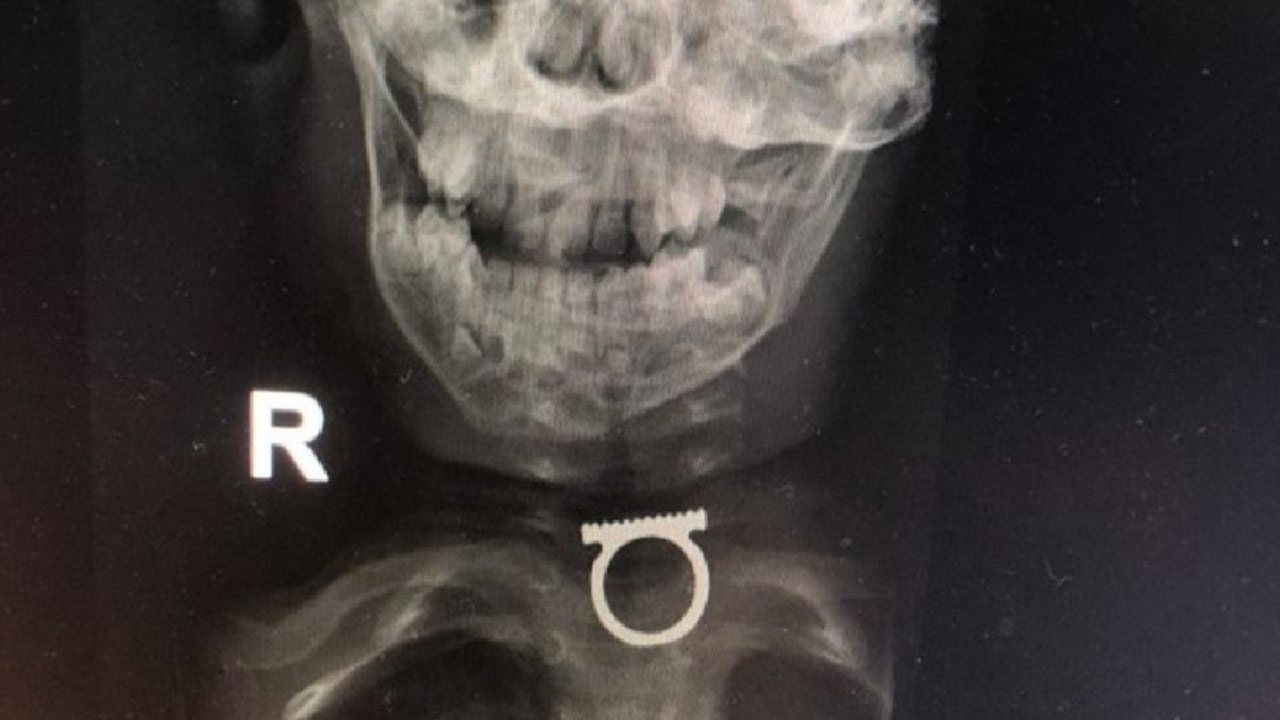

No obstante, la sorpresa de la madre y los médicos fue mayúscula, pues, tras someter al menor a una prueba de rayos X, estos pudieron identificar que el objeto que estaba trabado en la tráquea del niño era realmente un anillo.

A través de las redes sociales ha circulado una imagen de la prueba de rayos X que le fue practicada al menor, en la que se puede apreciar la magnitud del anillo depositado en su garganta, lo que ayuda a dimensionar el riesgo real al que estaba expuesto.